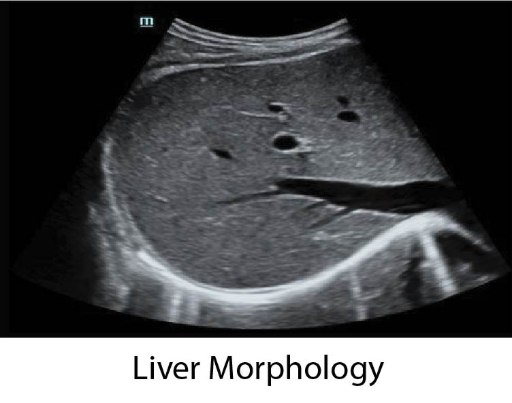

DP-50 Vet е балансирана ултразвукова система, максималното въплъщение на философията на Mindray Animal – качествена диагностика на достъпна цена.

Преносимия ехограф от ново поколение DP-50 Vet е с тънък и ергономичен дизайн, голям FullScreen монитор с качествен “В” и “цветен” образ, както и със стандартно включени множество възможности и софтуери.

Оборудван с PW доплер, Smart 3D и софтуери с автоматични измервания, DP-50 Vet надминава очакванията на всеки потребител. Компакният нов корпус, повишена мобилност и удобство при работа, правят модела подходящ за множество ветеринарни клинични нужди.